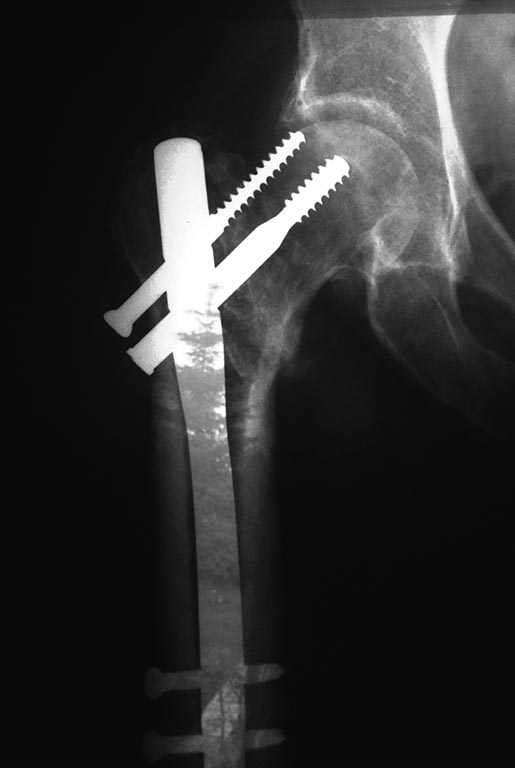

перелом бедра, остеосинтез кости блокируемым стержнем, состояние 3 месяца после операции. На этой же ноге установлен 4 года назад эндопротез ("со связочным аппаратом", так как была застарелая травма и пытались оперативно восстановить связки для стабильности колена) . Прикладываю снимок сразу после операции БИОС бедра и через 2месяца после ("болт сместился"), жалобы больной: три месяца на костылях, не получается полностью встать на ногу, нет стабильности , лежа не получается полностью разогнуть ногу, подтянуть ее боль сильная отдает в бедре. Коленный эндопротез ( по рентгену) не поврежден.

На снимке - идет прорезание имплантатов,скоро будет перфорирована суставная поверхность. Есть смещение по длине бедра.

Здесь надо делать или реостеосинтез, возможно, с вальгизирующей остеотомией бедра - если повреждение суставных поверхностей еще минимальное. Или эндопротезирование.